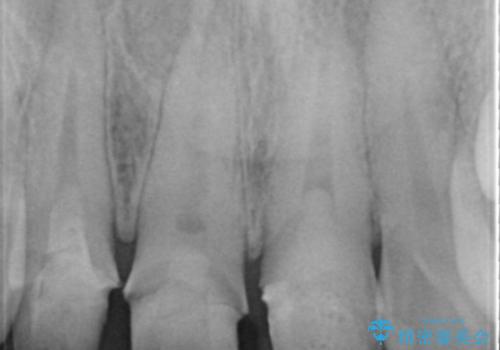

視診・X線検査・歯周組織検査より下記のような問題が列挙され、長期的な予後を見込むために一つづつ問題の解決を計ります。

・不十分な根管治療 →マイクロスコープを用いる精密根管医療

・歯の変色 →ジルコニアクラウンの製作

・歯肉縁下カリエス →部分矯正による歯の挺出・歯周外科